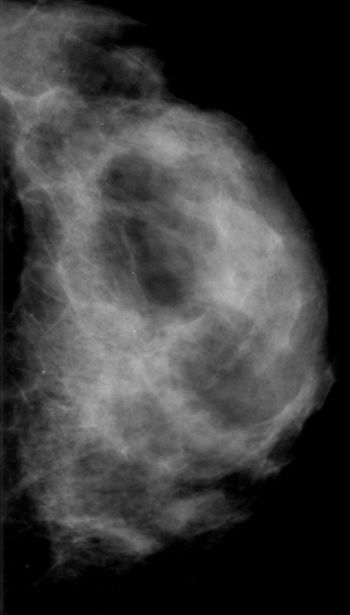

50-year-old patient presented for screening mammogram. Extremely dense breast tissue was noted.